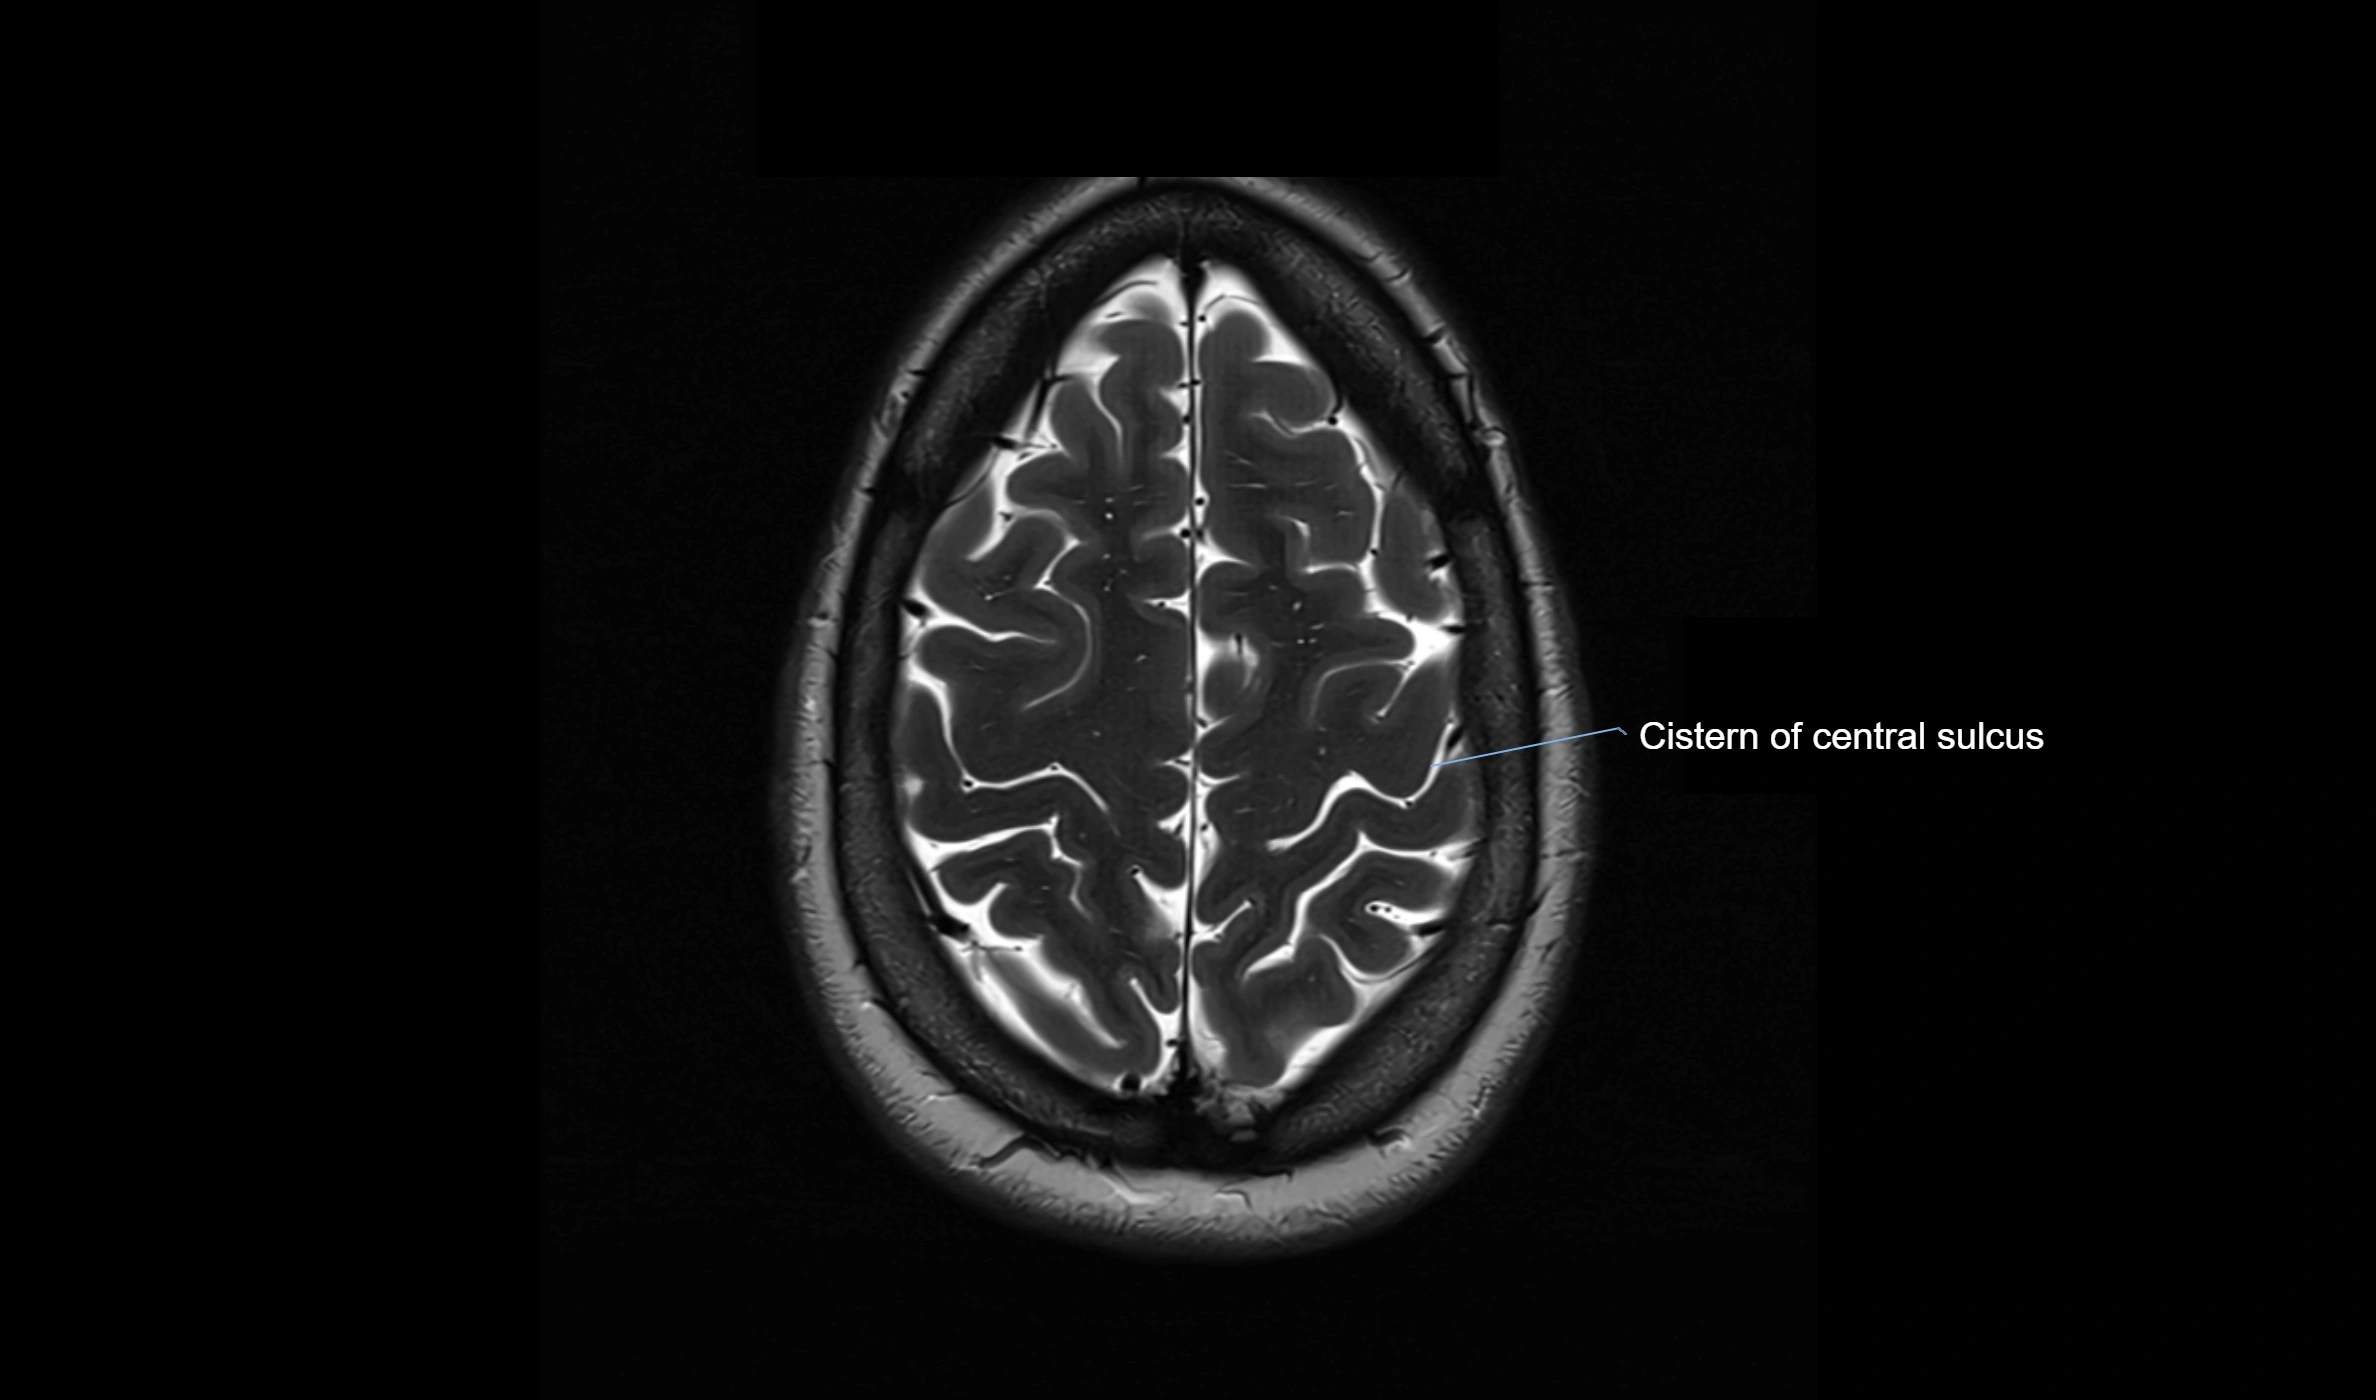

MRI images

image